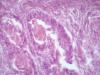

Опухоль матки |

Плоскоклеточный умереннодифференцированный рак,инвазия в железы.